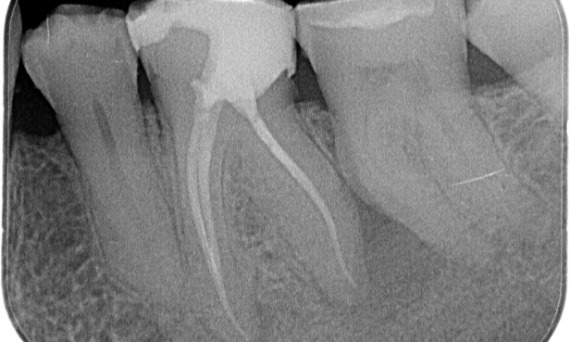

Après : La cavité d’accès a été réalisée de la manière la plus conservatrice possible. TruNatomy a été le système de choix en raison de l’âge du jeune patient. Nous devions préserver la dentine autant que possible afin d’augmenter la capacité de la dent à surmonter la charge occlusale et d’accroître la longévité de la restauration finale.